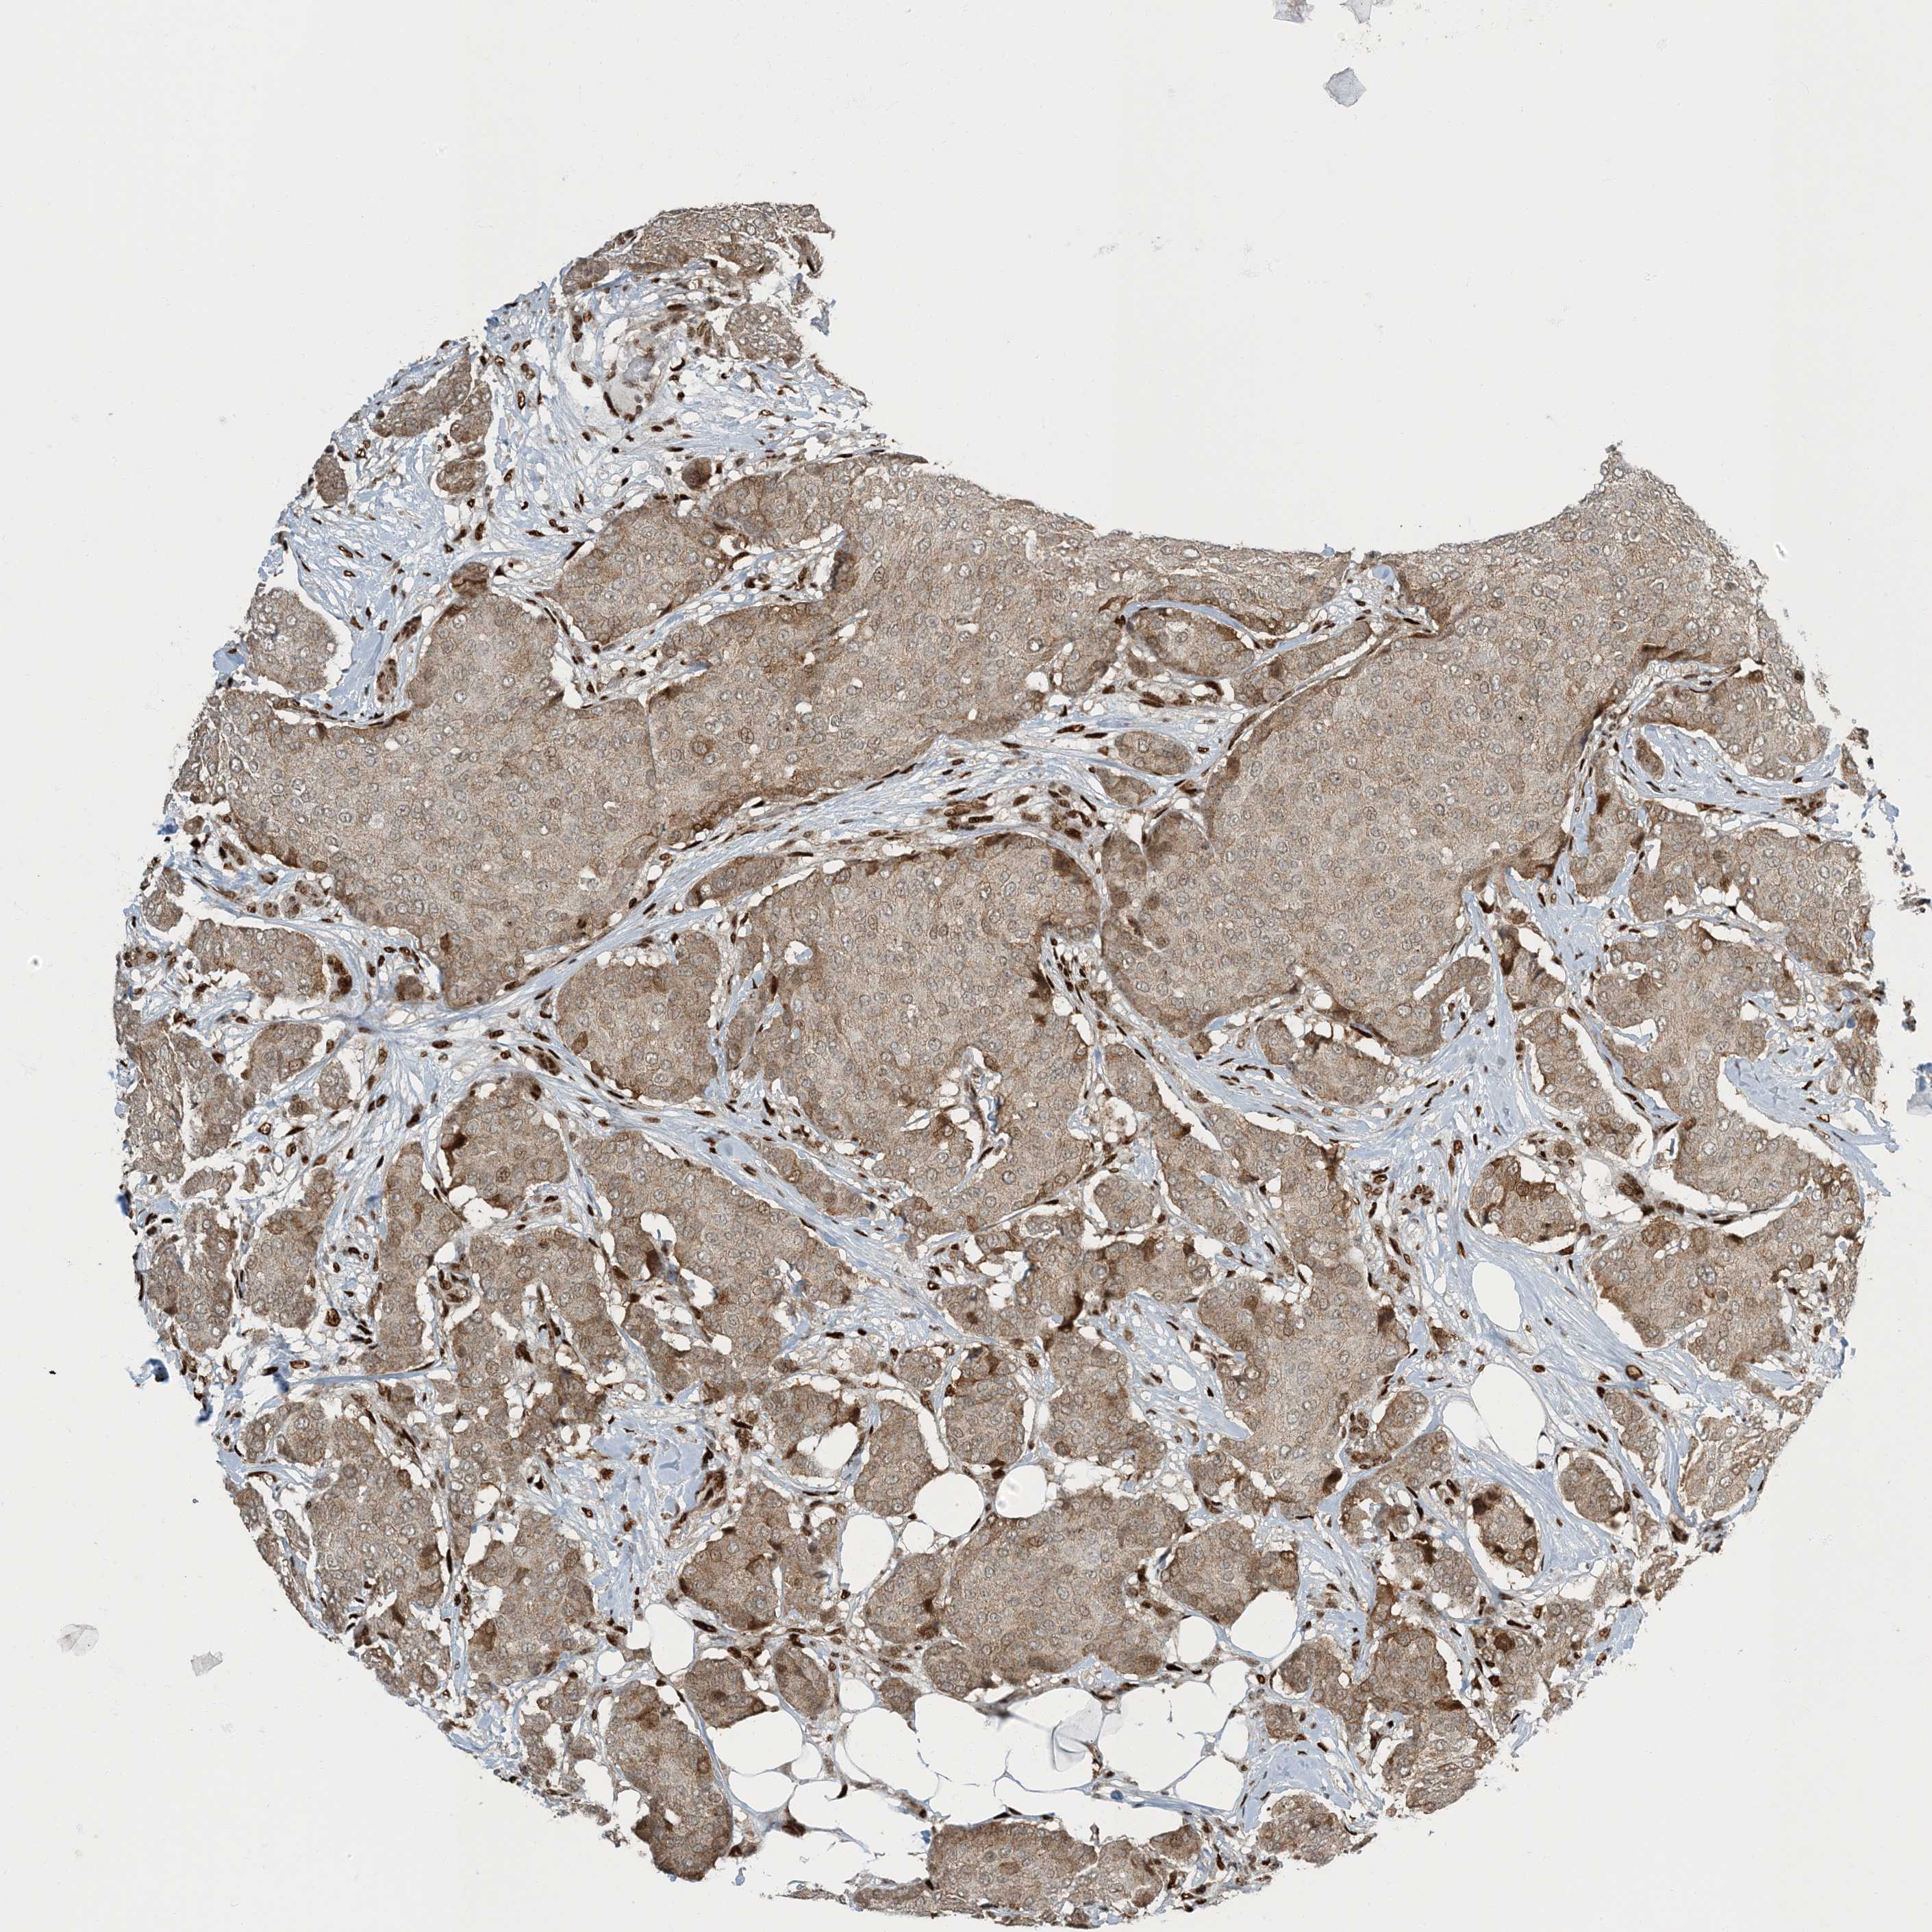

CANCER BREAST CANCER Show tissue menu

BRCA TCGA BRCA VALIDATION PROTEIN EXPRESSION